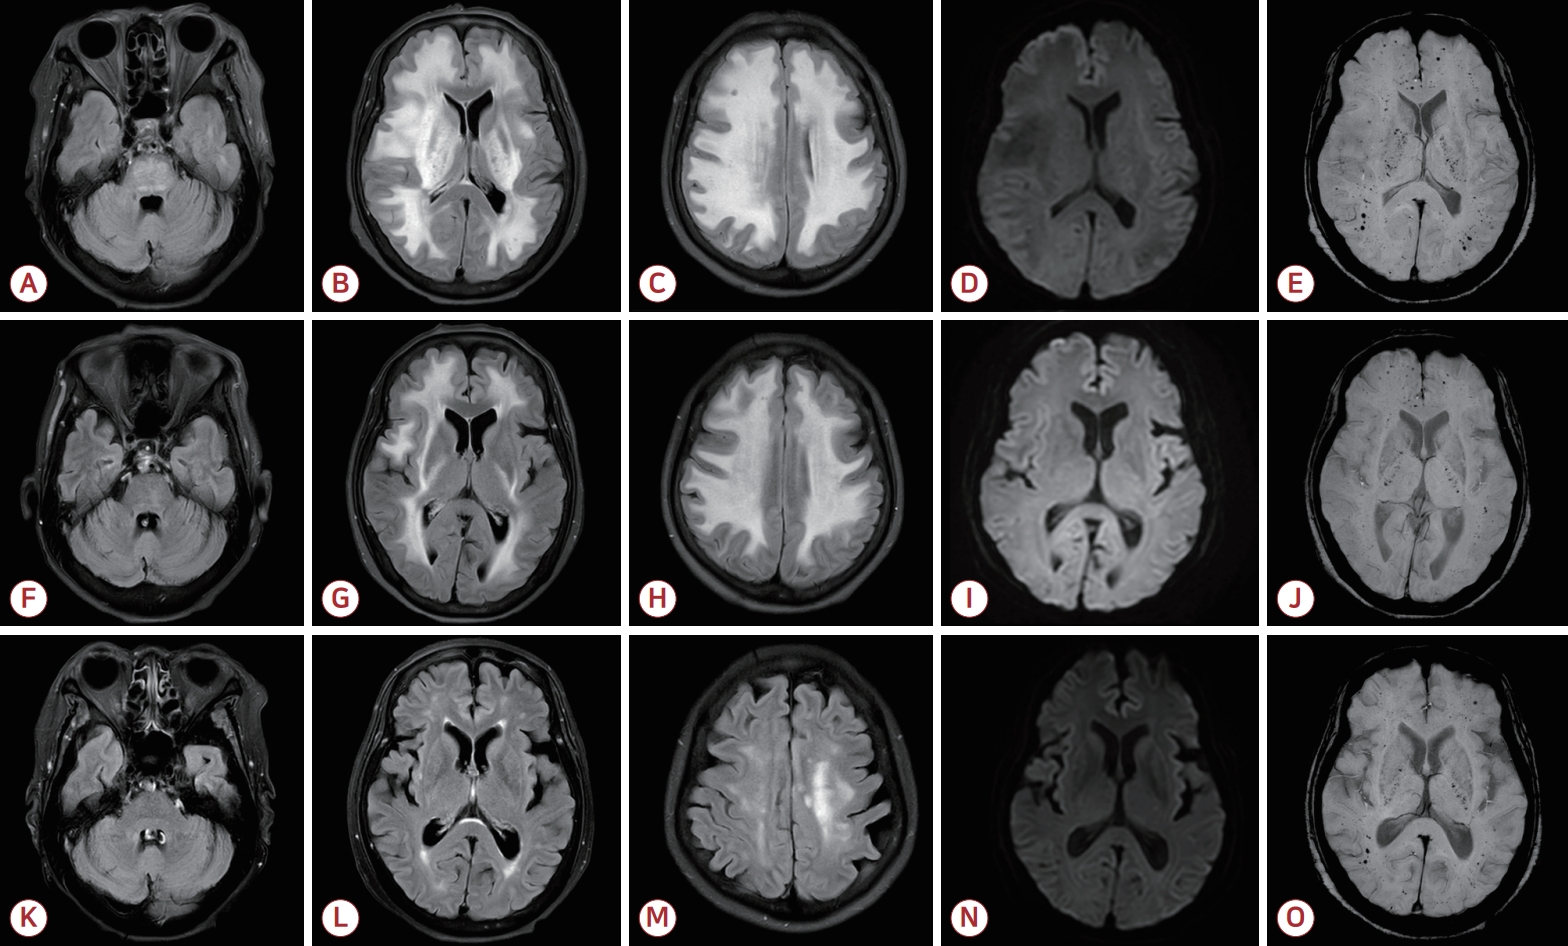

Acute Disseminated Cerebral Microbleeds in Patient with Pancytopenia2023 August;41(3)